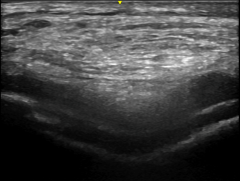

An ultrasound image of a large calcium deposit in the knee cartilage.

Large calcium deposit in the knee cartilage of a patient with CPPD arthropathy (“pseudogout”)